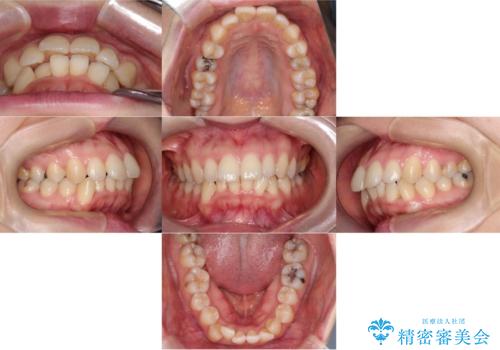

- 「歯のデコボコと前歯が出ているせいで口が閉じにくい」を主訴に来院された患者様です。

上下左右の4番(第一小臼歯)を抜歯をし審美ワイヤー装置で治療を行いました。

抜歯矯正により歯列のデコボコ(叢生)が改善し、前歯の突出も解消されたことで口元が下がり、すっきりとした印象となりました。